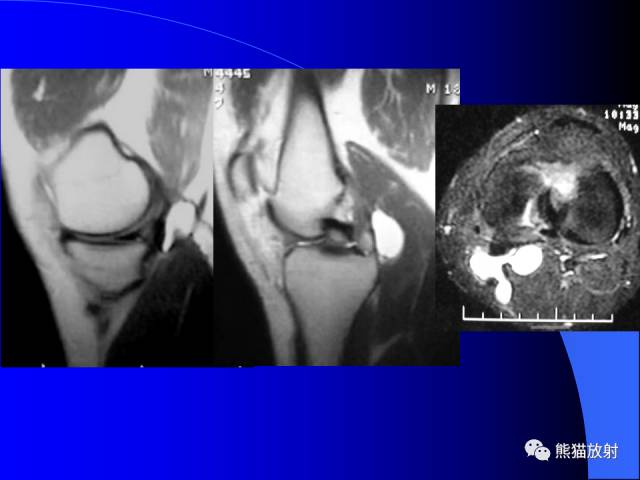

腘窝囊肿是膝关节周围最常见的囊肿。